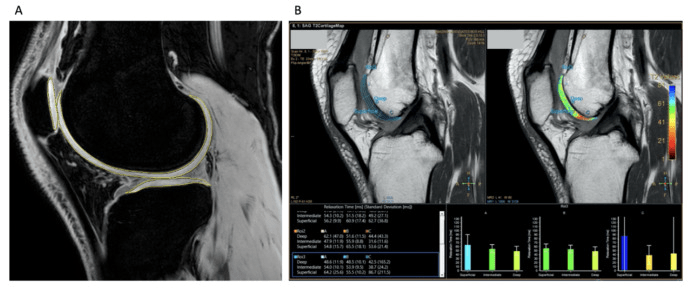

2024年7月26日,墨爾本干細(xì)胞研究中心牽頭在國際期刊《骨關(guān)節(jié)炎和軟骨開放》上發(fā)表了一篇關(guān)于《同種異體脂肪間充質(zhì)干細(xì)胞制劑治療膝關(guān)節(jié)骨關(guān)節(jié)炎的安全性和有效性》的I/IIa期隨機(jī)對(duì)照試驗(yàn)。[5]

這是一項(xiàng)單中心、雙盲、劑量遞增、隨機(jī)對(duì)照試驗(yàn)。40名患有中度膝關(guān)節(jié)骨關(guān)節(jié)炎的患者隨機(jī)接受單次關(guān)節(jié)內(nèi)注射MAG200(劑量組:10、20、50、100×106?細(xì)胞)或安慰劑。

- MAG200隊(duì)列報(bào)告的反應(yīng)者比例高于安慰劑組,并且疼痛癥狀有臨床和統(tǒng)計(jì)學(xué)顯著改善,所有KOOS分量表均有臨床相關(guān)改善。(圖2)

- MAG200顯示出優(yōu)于安慰劑的可重復(fù)治療效果,這對(duì)于10×106劑量組的疼痛具有臨床相關(guān)性,對(duì)于20×106和100×106劑量組的功能具有臨床相關(guān)性。

- 在MAG200 10、20和100 × 106劑量組中,觀察到疾病改善趨勢(shì),膝關(guān)節(jié)軟骨總體積有所改善,而安慰劑組中骨關(guān)節(jié)炎有輕微改善。

- 治療耐受性良好,未發(fā)生與治療相關(guān)的嚴(yán)重不良事件。

綜上所述,在MAG200 10、20和100 ?× ?106劑量組中,觀察到疾病改善趨勢(shì),膝關(guān)節(jié)軟骨總體積有所改善,而安慰劑組中骨關(guān)節(jié)炎進(jìn)展不顯著。